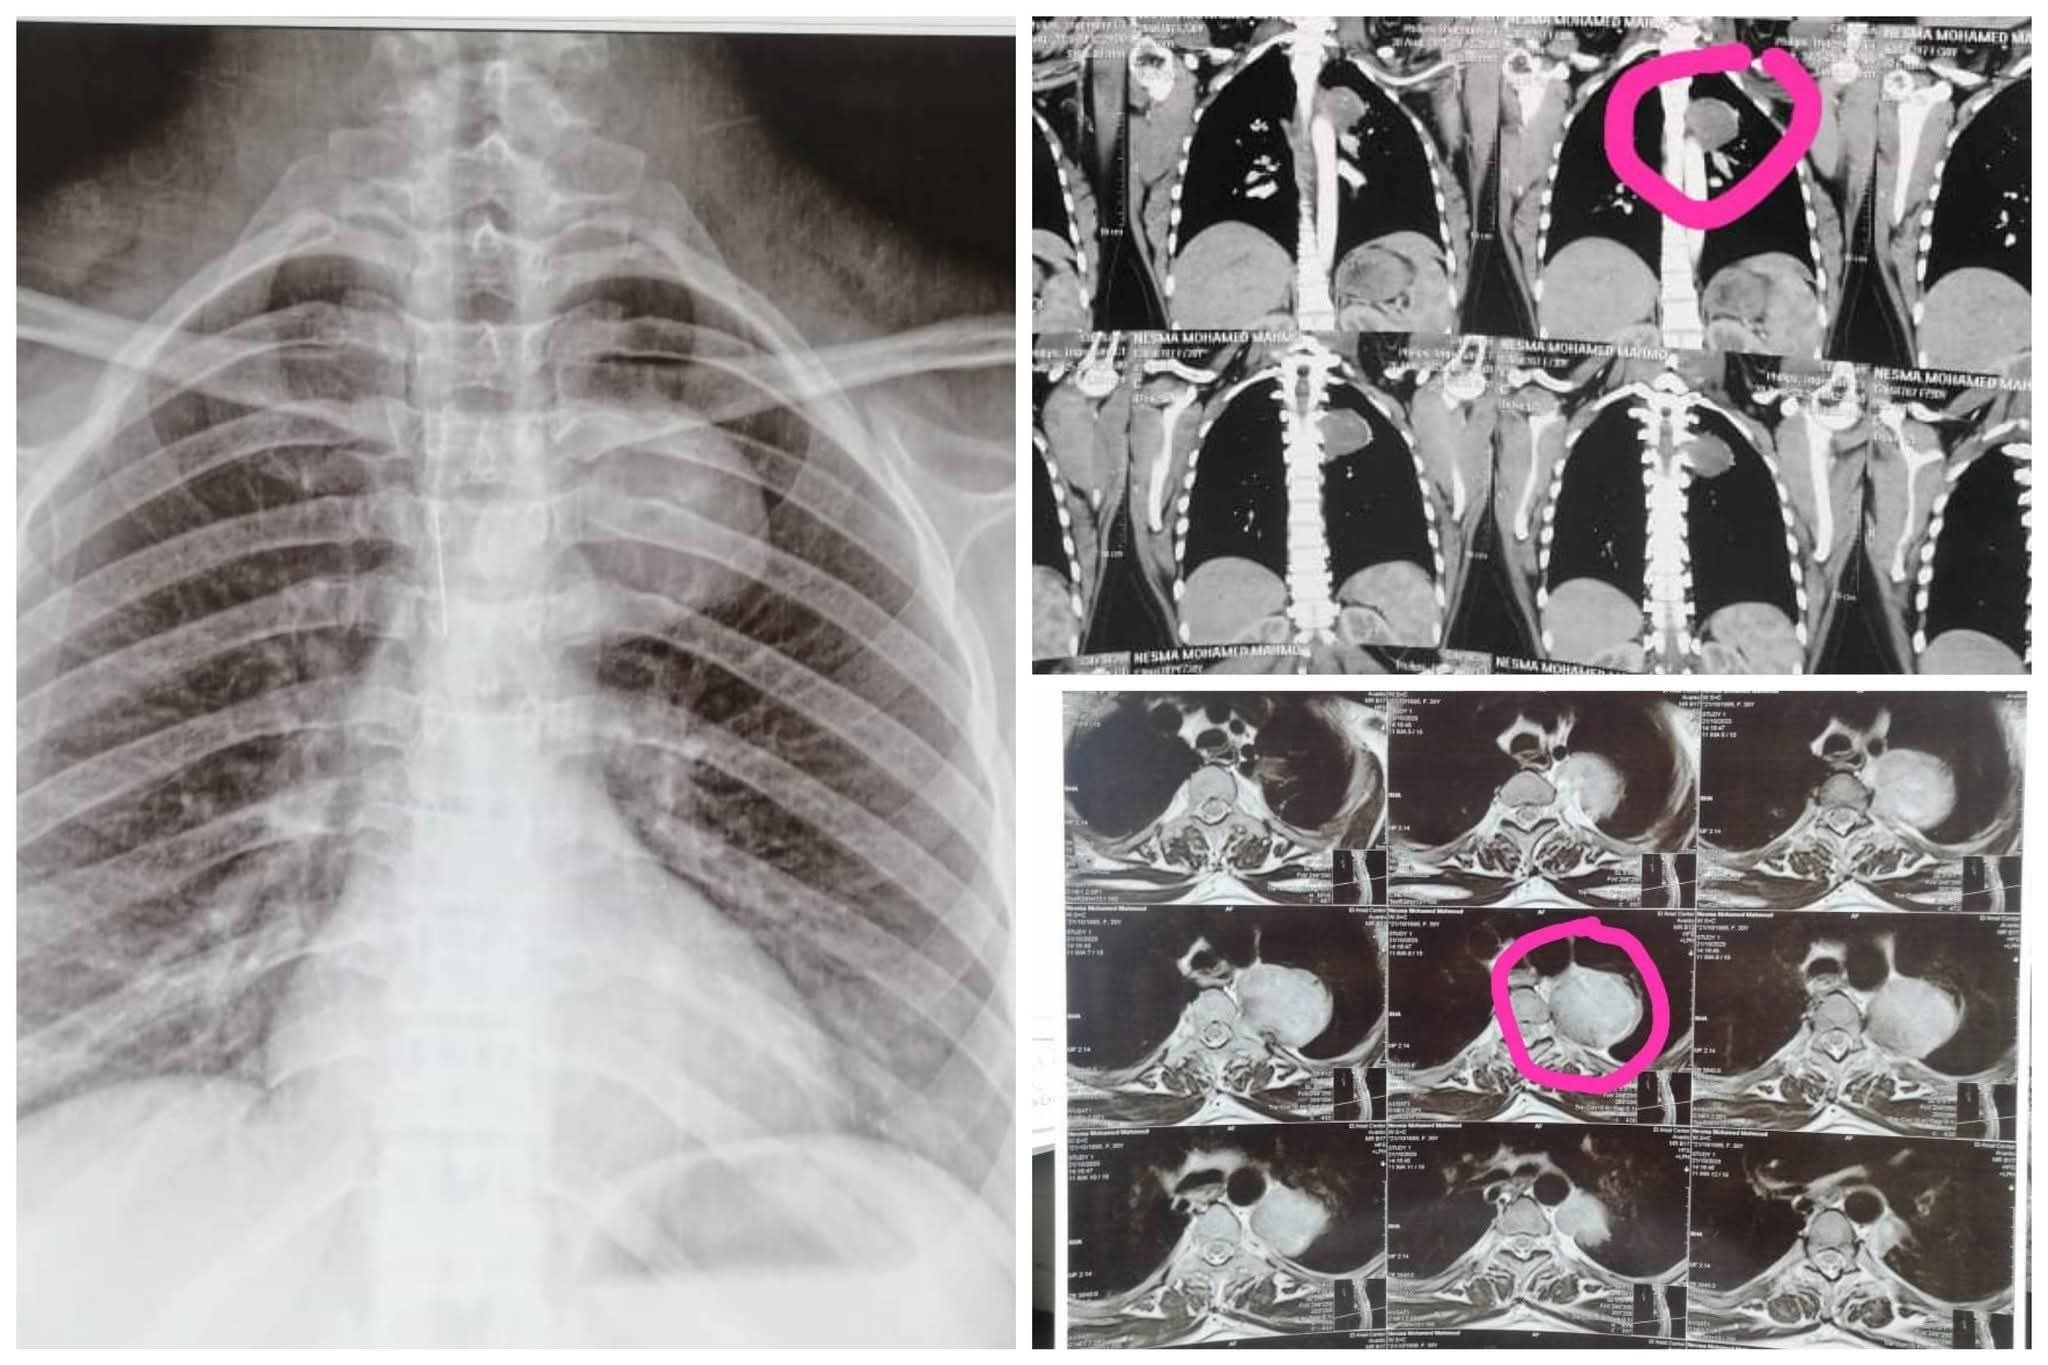

كان مستشفى الأمراض العصبية والنفسية وجراحة المخ والأعصاب برئاسة الأستاذ الدكتور طارق راجح، قد استقبل سيدة تبلغ من العمر ٢٥ عاما، حامل في شهرها الأول، وتعاني من إلتهابات رئوية متكررة، وبعد فحصها من قبل فريق من المتخصصين #بقسم_الأمراض_الصدرية، تحت إشراف الأستاذة الدكتورة صفاء وافي، وضم الدكتورة صفاء عبد الجيد، استشاري الأمراض الصدرية، والطبيب يوسف ثروت، طبيب مقيم بالقسم، بمشاركة الطبيبة شروق كيلاني، مدرس مساعد بقسم طب القلب، أظهرت الأشعات وجود ورم معقد بالعمود الفقري ممتد إلى الرئة.

تشكل على الفور فريق طبي من #قسم_جراحة_المخ_والأعصاب تحت إشراف الأستاذ الدكتور محمد السيد رئيس القسم وضم كل من، الدكتور علي أحمد عبد العليم، مدرس بالقسم، والطبيب محمد الغرياني، مدرس مساعد بالقسم، وفريق طبي من #قسم_جراحة_القلب_والصدر تحت إشراف الأستاذ الدكتور محمد عياد، رئيس القسم ومدير مستشفى القلب، وضم كل من، الأستاذ الدكتور حسين الخياط، أستاذ جراحة القلب والصدر، والطبيب محمد ربيع، مدرس مساعد بالقسم، والطبيب أحمد يونس، طبيب مقيم بالقسم، يعاونهم فريق طبي من #قسم_التخدير جاء تحت إشراف الأستاذة الدكتورة هالة سعد، وضم، الدكتور هيثم محمد، مدرس بالقسم، وقاموا بإجراء العملية باستخدام تقنية التدخل المحدود، لتقليل الضرر، عن طريق فتحة صغيرة بالظهر (حوالي ٣ سم)، تم من خلالها التدخل بـالميكروسكوب الجراحي عالي الدقة لاستئصال الجزء الشوكي من الورم مع الحفاظ التام على الأعصاب المحيطة، وفتحة أخرى بالصدر ٣ سم تقريبا، تم استخدام منظار الصدر الجراحي للوصول إلى الجزء الممتد للرئة واستئصاله، مع الحفاظ على وظائف الرئة.

وبفضل دقة التخطيط والمهارة الفائقة للفريق الطبي، تم استئصال الورم بشكل كامل بنجاح، مع الحفاظ على سلامة الأعصاب، الرئة، والجنين، وتماثلت المريضة للشفاء، وغادرت المستشفى بعد خمسة أيام فقط من إجراء العملية، وهي بصحة جيدة ومستمرة في متابعة حملها.